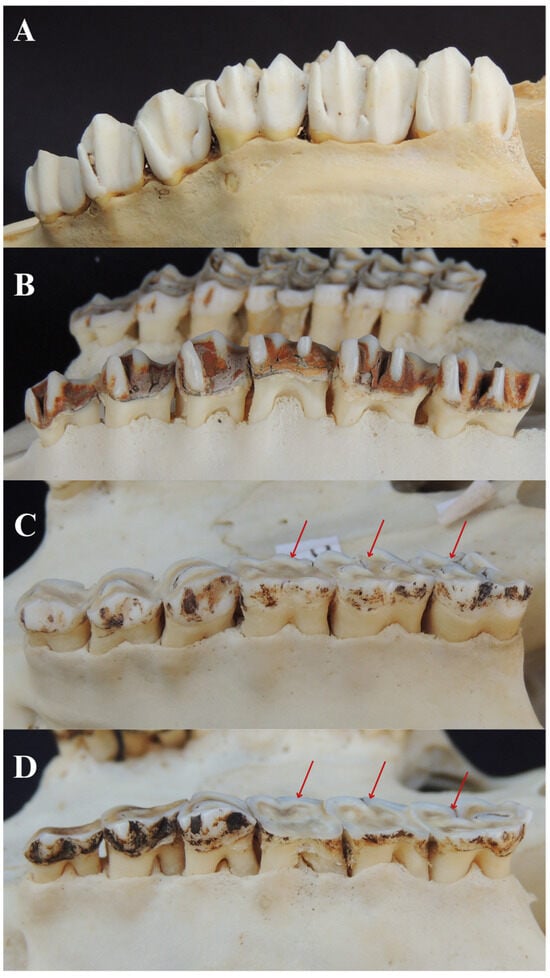

3.6.1. Fenestration

3.6.2. Dehiscence

3.5.6. Furcation Exposure

3.6. Bone Lesions